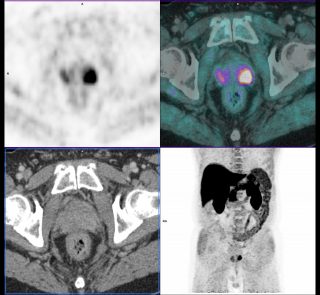

PET Scan à la Fluorocholine

Bilan d’extension et de rechute d’un adénocarcinome prostatique.